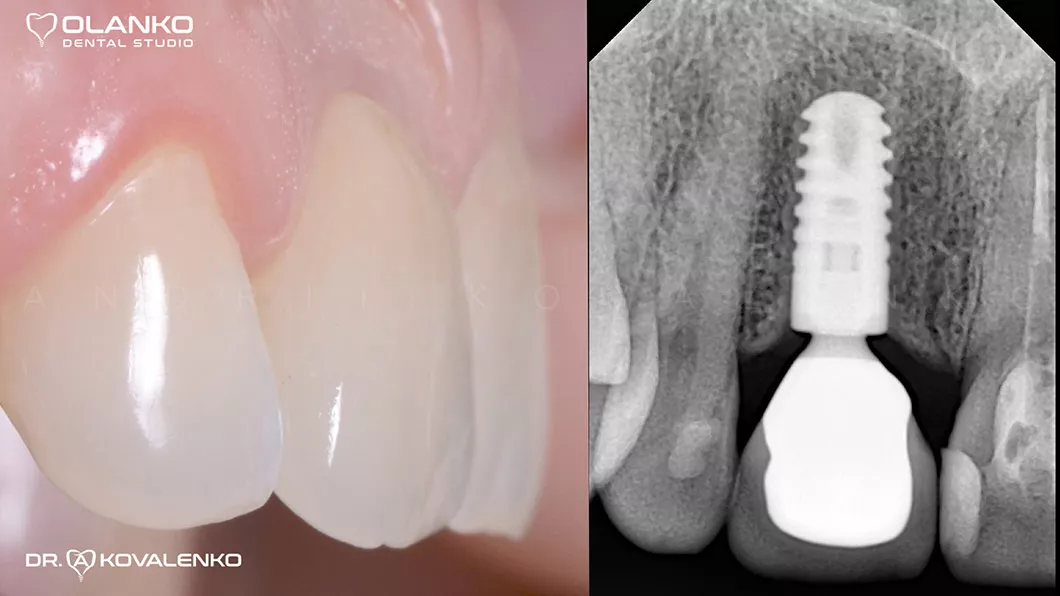

Изготовлена постоянная керамическая коронка

Клинический случай 5 имплантация зубов

Вид после фиксации постоянной керамической коронки